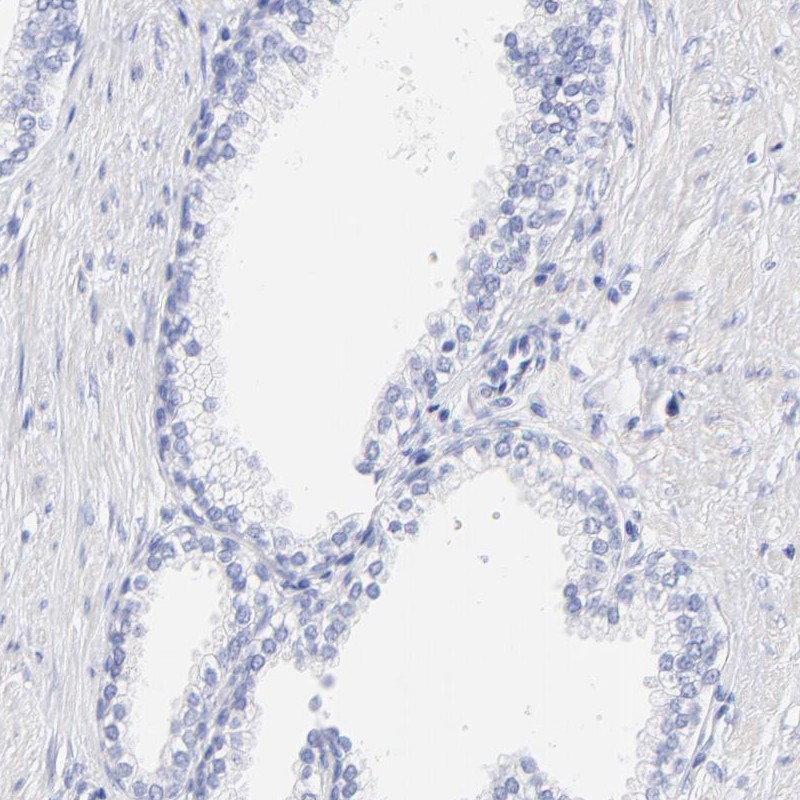

Immunohistochemistry analysis in human placenta and prostate tissues using Anti-C1QTNF6 antibody. Corresponding C1QTNF6 RNA-seq data are presented for the same tissues.